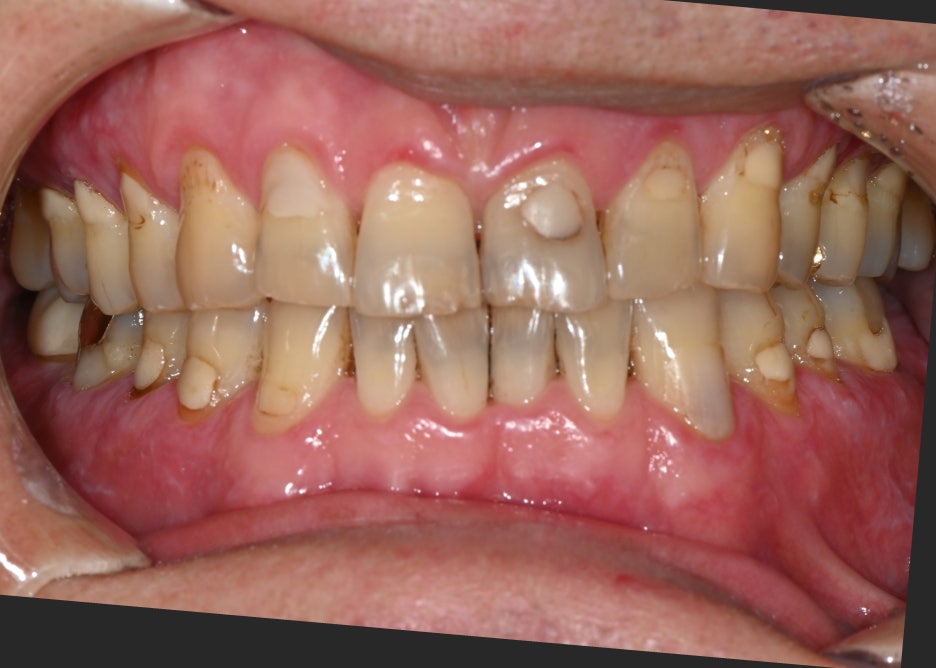

안녕하세요! 서울오브치과병원입니다. 오늘은 왼쪽 아래 어금니 임플란트 수술 사례를 소개해드리겠습니다. 환자분은 오래 전 발치 후 방치해 두었던 자리 때문에 씹는 불편함이 생겨 치료를 원하셨습니다. 초진 내원 당시 왼쪽 아래 어금니를 예전에 뽑았는데 요즘은 반대쪽으로만 씹다 보니 턱도 불편해요 환자분은 “왼쪽...

환자분은 오래 전 발치 후 방치해 두었던 자리 때문에

씹는 불편함이 생겨 치료를 원하셨습니다.

초진 내원 당시

왼쪽 아래

어금니를 예전에 뽑았는데

요즘은 반대쪽으로만 씹다 보니

턱도 불편해요

환자분은 “왼쪽 아래

요즘은 반대쪽으로만 씹다 보니 턱도 불편하다”는

주호소로 내원하셨습니다.

치아가 오랫동안 결손된 상태라 양쪽 균형이 맞지 않고

음식물이 자주 끼면서 잇몸도 불편했다고 말씀하셨습니다.